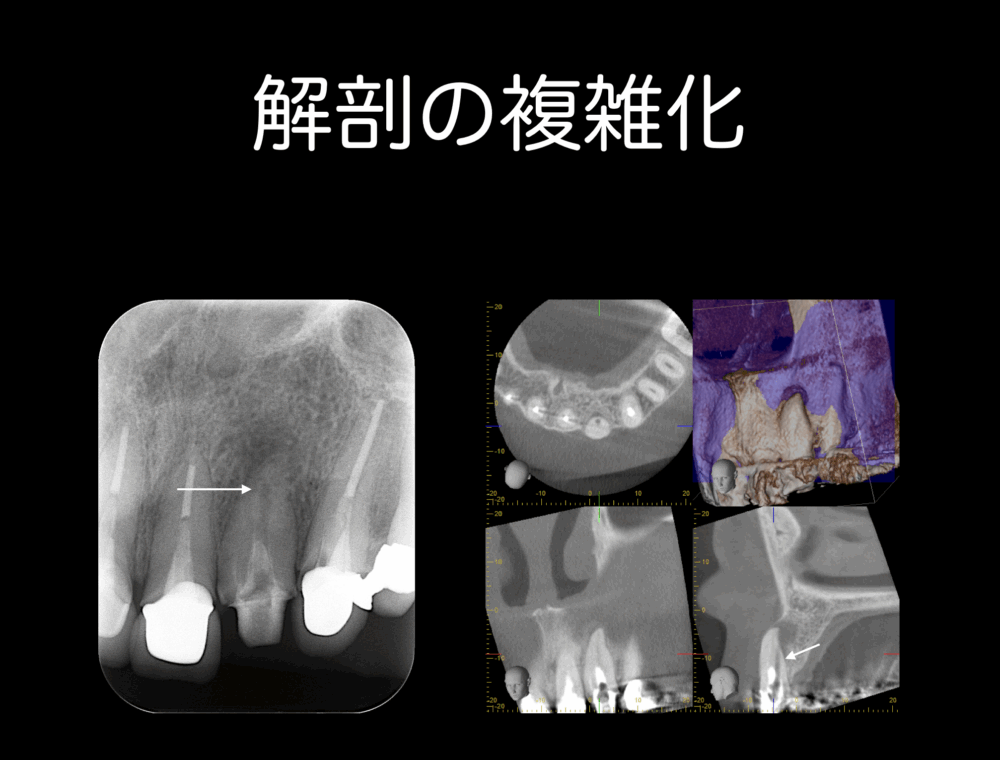

- 解剖学的な構造が複雑だと判断した時

デンタルで根管が理想とは異なる走行をしているとき、事前にCTを撮影しておくと、治療をスムースに進めることができます。この症例は、口蓋側にトランスポーテーションを起こしていることがわかりました。